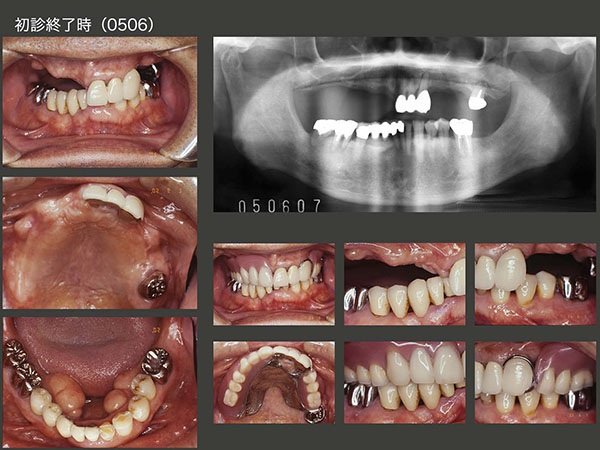

2005年11月初診,53歳女性.左上コーヌス義歯は,7年前に他院にて製作.一般的には上下顎に歯が沢山残っている右側で咀嚼すると思われるが,本人は元々左側咬みで,義歯を入れてからも左側の方が咬みやすいとおっしゃっていた,珍しいケース.初診時は,左下5のう蝕処置のみを行い,06年5月から右下5〜7の治療を行った.スライド中段は,06年5月の上顎の状態.

特に問題なく経過したが,12年12月,左上4に歯根破折が生じ,自発痛も生じたので,抜歯せざるを得なかった.左上3のみの片側処理の義歯は無理なため,抜歯と同時に右上5にクラスプを付与した大連結装置を追加した.しかし,口蓋を覆ったため異物感,発音障害を強く訴えられた.

2014年8月,今回の治療が一区切りついた時の状態.この症例で片側処理の補綴を行う場合は,インプラントの助けが必要となる.植立位置は,上顎洞の前後とし,7mmおよび8.5mmの長さのインプラントを用いた.固定式のブリッジでも補綴処置は可能であるが,過去に可撤式の義歯を使用していた経験があること,また支台の清掃性を重視したいことから,コーヌス義歯を選択した.